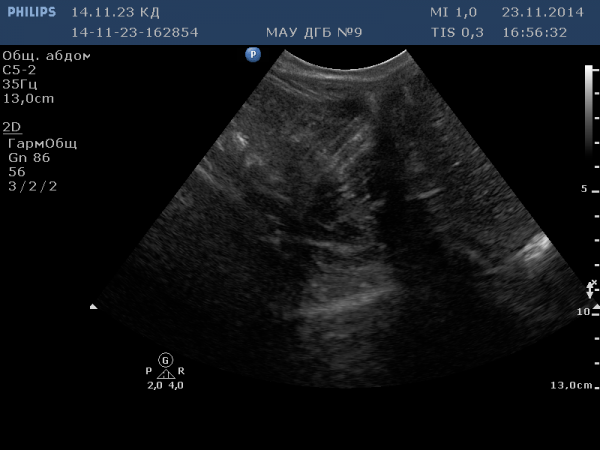

Как-будто кот стягивает на себя край скатерти

Как-будто кот стягивает на себя край скатерти ]

как будто чужой, смотрит тебе прямо в душу

А что это за структуры вообще? как вы их трактуете?